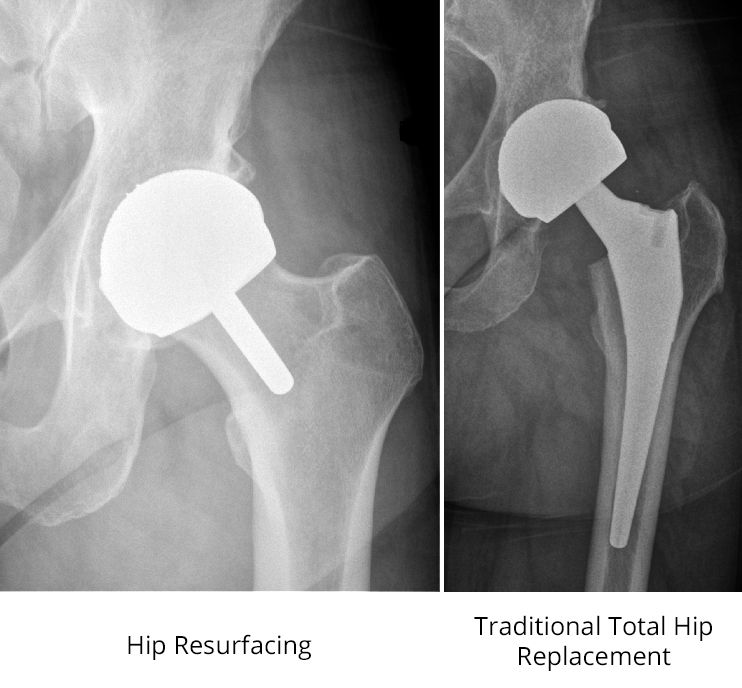

7272020 The hip joint is a ball and socket joint. During the initial development of hip replacement the surgeons tried to make the implants which mimic the size of the natural femoral head. 7202012 Hip replacement surgery is an operation used to replace the damaged ball-and-socket with new and durable artificial synthetic parts that mimic the ball-and-socket.

The size of the ball of the natural hip joint femoral head varies and usually ranges from 40 to 54 mm with smaller sizes in females. The hip replacement surgery removes damaged bone and cartilage from the hip joint and replaces it with an artificial joint prosthesis.